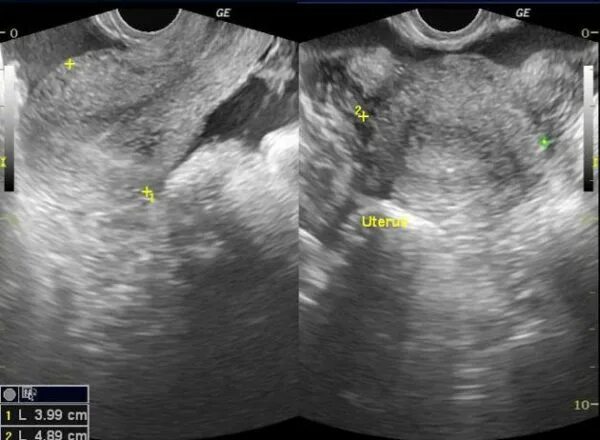

Яичник 8 см